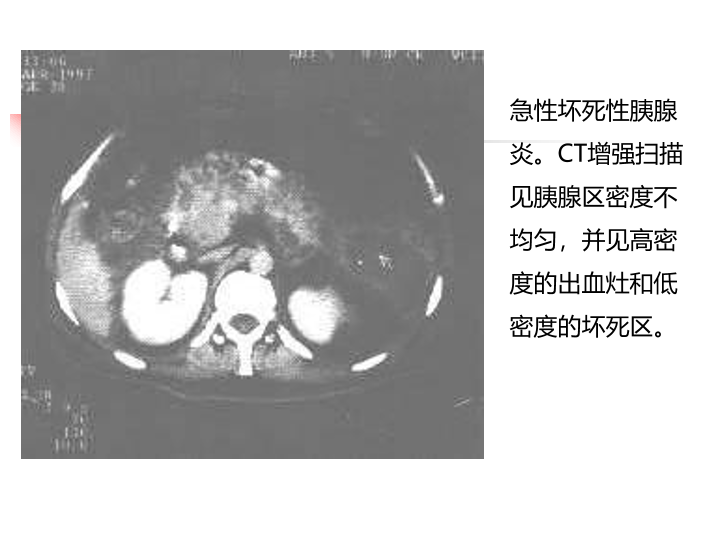

急性胰腺炎诊治